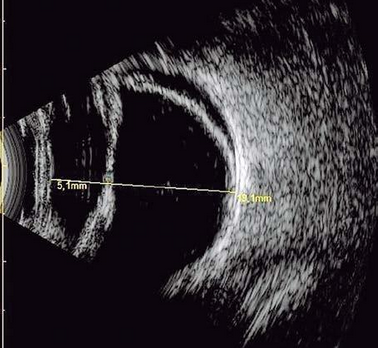

Ultrassonografia Ocular

Exame de imagem que avalia estruturas internas do olho. É Indicado quando a visualização direta é dificultada por catarata avançada, hemorragia vítrea ou opacidades. Para o diagnóstico de possíveis descolamentos de retina, patologias vitreas e tumores intraoculares